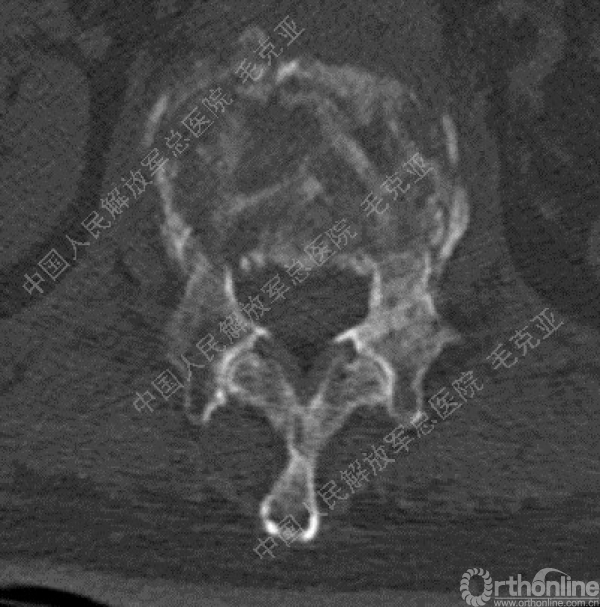

导语:随着社会老龄化的不断加速,骨质疏松性椎体压缩骨折作为一种普遍存在的老年骨科疾病已经成为现今骨科界的一个热点话题。传统的保守疗法治疗效果不佳,而现有的椎体增强技术又具有多种风险和缺陷。针对这种现状,中国人民解放军总医院毛克亚教授提供了一种新的解决方法。